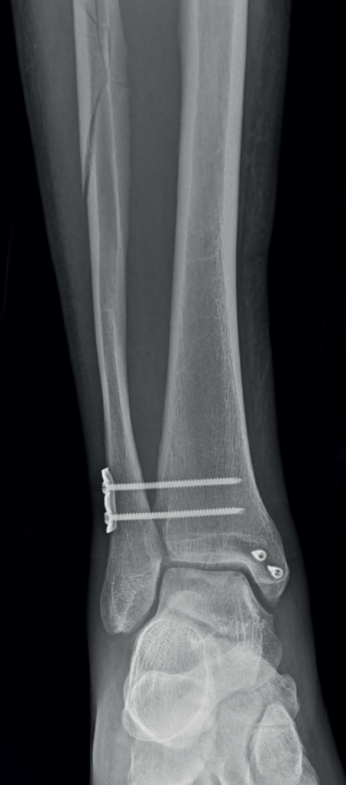

Posteriormente, se realiza una incisión lateral de tobillo de 4 a 5 cm centrada en la sindesmosis tibiofibular. Se confirma la lesión sindesmal bajo visión directa y mediante el test del gancho. Se efectúa el desbridamiento de posibles fragmentos óseos interpuestos entre la tibia y la fíbula. La maniobra de reducción consiste en la tracción en el eje y la rotación interna de la fíbula mediante una pinza Backhouse, manteniendo en posición con un clamp óseo entre la tibia y la fíbula distal exactamente en el eje de la articulación tibiotalar. La posición correcta de la fíbula en su incisura se logra al alinear el tubérculo de Tillaux-Chaput con el tubérculo de Le Fort-Wagstaffe en el plano axial bajo visión directa. Se constata la reducción tibiofibular bajo intensificador de imágenes. Se realiza la fijación sindesmal con una placa de 3,5 mm con 2 tornillos tricorticales de posición (Figura 2).

En todos los pacientes de esta serie utilizamos el mismo método de fijación sindesmal, 1 placa de 3,5 mm con 2 tornillos tricorticales de posición según la técnica quirúrgica descrita previamente. En tan solo 2 casos se utilizó 1 arpón de doble sutura; en el resto de las lesiones del ligamento deltoideo se emplearon 2. Todas las fracturas de maléolo medial de fijaron con 2 tornillos de rosca parcial de 4,0 mm. Tres fracturas (15,7%) de tipo 2 del maléolo posterior requirieron ser fijadas a través de un abordaje posterolateral al hallarse desplazadas más de 3 mm en la tomografía preoperatoria.